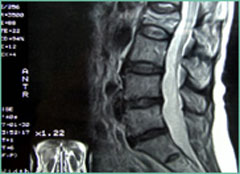

ヘルニアは飛び出るという意味ですのでレントゲンでそれらしい状態が映っていたり、MRIでみつけることができ画像診断が行われます。

ですが最近の医学の見解では、「画像や問診から病名はつけることができるが、実際は画像と原因が明快に一致する例は少ない」と報告されているようです。

無症状の人でも、腰の画像診断をすると、3割くらいの方にヘルニアが見つかり、逆に痛みを訴えていても、半数近くは画像上の異常が見つからないという報告もあります。